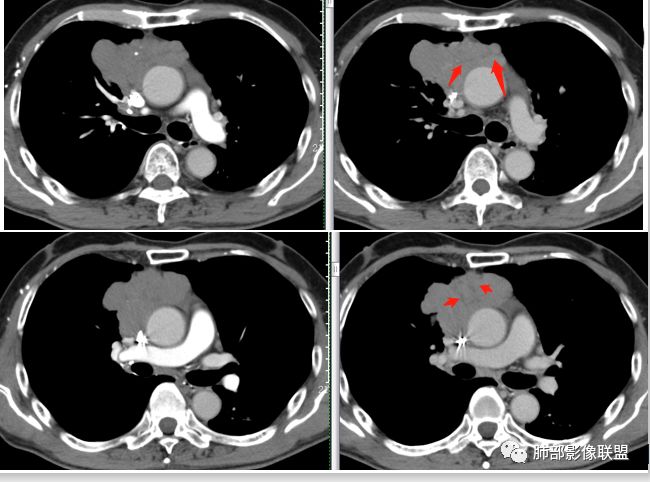

马春平(张家港市一院胸外科): 老年男性,前纵隔占位,中央细沙钙化,右上支气无阻塞,均匀强化、分叶,与心包广基接触,纵隔鳞癌>胸腺瘤

哞: 上腔侵犯,考虑侵袭性胸腺瘤,或者癌

红星: 定位前上纵隔占位性病变,考虑侵袭性胸腺瘤

一切∮随缘: 病灶主体位于前纵隔,向主动脉周围蔓延,与周围组织间隙清楚,病灶形态较软,与胸膜交界尚可,部分支气管受压截断,平扫密度欠均匀,内部可见低密度钙化,增强后轻度均匀强化,坏死不明显,考虑:1:畸胎瘤2:胸腺瘤3:淋巴管瘤

小兜:老年男性,受凉后发烧就诊,前上纵隔不规则肿块,分叶,内见结节状钙化,包绕上腔静脉及左头臂静脉,挤压右肺,增强后轻度强化,内部可见多发低密度区,双侧内乳血管未见明显增粗?考虑为恶性,胸腺癌可能

张小兵: 前纵隔不规则肿块,分叶、包绕血管,内见点状钙化及裂隙样低密度区,轻度强化,倾向恶性,胸腺癌可能,鉴别淋巴瘤。

王秀仙: 前纵隔占位,边缘结节状分叶,多发沙粒状钙化,内部见裂隙状分隔,周围肺组织推移,与心包广基接触,中度强化,病灶左后方心包内积液,叶间胸膜多发结节,考虑纵隔胸腺瘤B3。

丽: 老年男性,咳嗽发热,前纵隔不规则软组织肿块,与纵隔面呈宽基底,周围脂肪间隙消失,边缘分叶、膨隆,内可见点状钙化,增强后轻度强化,考虑胸腺癌

流心明智: 老年男性,前上纵隔不规则肿块,分叶,中央点状钙化与裂隙样低密度区,上腔受侵,与心包广基接触,轻度均匀强化。考虑:胸腺Ca?鉴别淋巴瘤。

前纵隔分叶状软组织团块,包绕血管,周围脂肪间隙消失,其内可见钙化,增强扫描轻中度强化。首先考虑侵袭性胸腺瘤,不除外纵隔型肺癌。